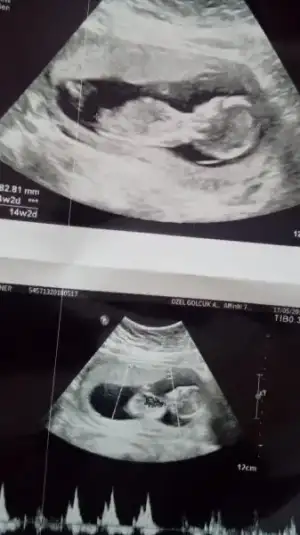

Kız sanki. 14. Hafta göstermedi mi?Hadi bende paylaşıyım ultrasonumu :) cinsiyet tahminlerinizi bekliyorum hatunlar

Kız sanki. 14. Hafta göstermedi mi?

aynen sağlıklı ve hayırlı bir evlat olsunda inşallah hiç farketmez:)hadi insaallh cnmm saglikli olsunda hic onmli degill ama biz merakli anneleriz yaa